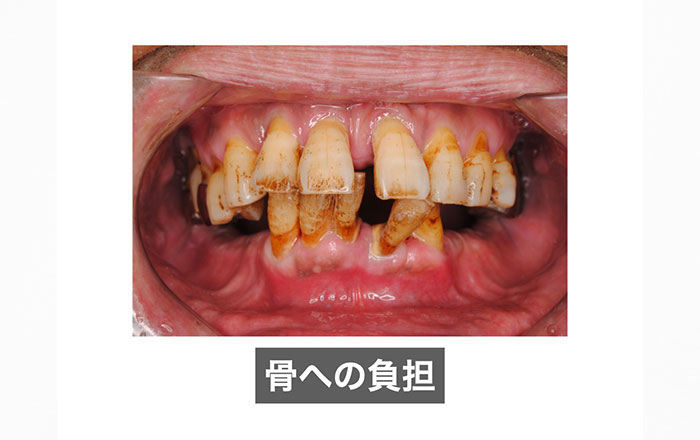

2)骨への悪影響

・歯周病が悪化しやすくなる

・歯周病で既に骨が破壊されている人はさらに進行する